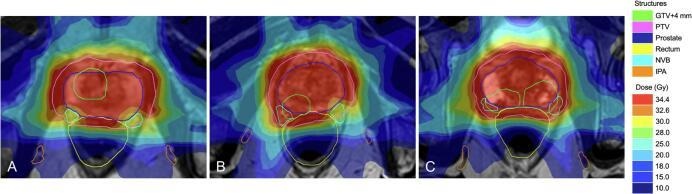

Erectile dysfunction is a common adverse effect of external beam radiation therapy for localized prostate cancer (PCa), likely as a result of damage to neural and vascular tissue. Magnetic resonance-guided online adaptive radiotherapy (MRgRT) enables high-resolution MR imaging and paves the way for neurovascular-sparing approaches, potentially lowering erectile dysfunction after radiotherapy for PCa. The aim of this study was to assess the planning feasibility of neurovascular-sparing MRgRT for localized PCa.

MATERIALS AND METHODS

Twenty consecutive localized PCa patients, treated with standard 5×7.25 Gy MRgRT, were included. For these patients, neurovascular-sparing 5×7.25 Gy MRgRT plans were generated Dose constraints for the neurovascular bundle (NVB), the internal pudendal artery (IPA), the corpus cavernosum (CC), and the penile bulb (PB) were established. Doses to regions of interest were compared between the neurovascular-sparing plans and the standard clinical pre-treatment plans.

RESULTS

Neurovascular-sparing constraints for the CC, and PB were met in all 20 patients. For the IPA, constraints were met in 19 (95%) patients bilaterally and 1 (5%) patient unilaterally. Constraints for the NVB were met in 8 (40%) patients bilaterally, in 8 (40%) patients unilaterally, and were not met in 4 (20%) patients. NVB constraints were not met when gross tumor volume (GTV) was located dorsolaterally in the prostate. Dose to the NVB, IPA, and CC was significantly lower in the neurovascular-sparing plans.

勃起功能障碍是局限性前列腺癌(PCa)外照射放疗的常见不良反应,可能是神经和血管组织受损所致。磁共振引导的在线自适应放疗(MRgRT)可实现高分辨率磁共振成像,为保留神经血管的方法铺平了道路,有可能降低PCa放疗后的勃起功能障碍。本研究的目的是评估保留神经血管的MRgRT用于局限性PCa的计划可行性。

材料与方法

纳入连续20例接受标准5×7.25 Gy MRgRT治疗的局限性PCa患者。为这些患者制定了保留神经血管的5×7.25 Gy MRgRT计划。确定了神经血管束(NVB)、阴部内动脉(IPA)、海绵体(CC)和阴茎球部(PB)的剂量限制。比较了保留神经血管的计划与标准临床治疗前计划中感兴趣区域的剂量。

结果

所有20例患者的CC和PB均满足保留神经血管的限制。对于IPA,19例(95%)患者双侧满足限制,1例(5%)患者单侧满足限制。NVB的限制在8例(40%)患者双侧、8例(40%)患者单侧得到满足,4例(20%)患者未得到满足。当大体肿瘤体积(GTV)位于前列腺背外侧时,NVB限制未得到满足。保留神经血管的计划中NVB、IPA和CC的剂量显著降低。